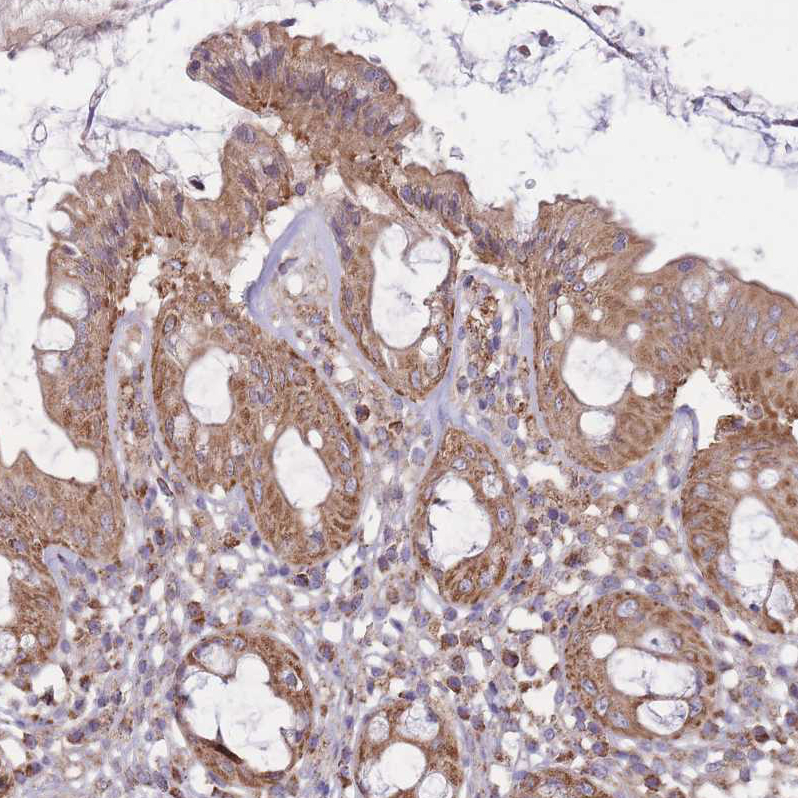

Immunohistochemical staining of human rectum shows moderate granular cytoplasmic positivity in glandular cells.